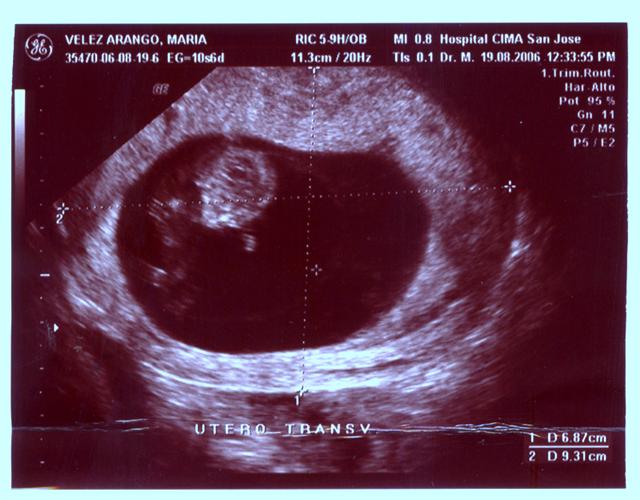

Ya muchos de uds saben que hoy pasamos un pequeño susto y tuvimos que ir a emergencias en el hospital. Afortunadamente resulto ser solo eso, «un susto» y todos nos encontramos muy bien de salud! Yo estoy fuerte y sano como siempre, mi corazoncito a 144 latidos x minuto. Hoy mido 3.9 cms de la cabeza hasta mi colita como pueden ver en mi segunda fotografÃa titulada «Ãºtero transv». Les cuento que mientras me hacÃan mi segundo estudio fotográfico (léase 2do ultrasonido) pose de muchas formas para mis papitos. Les mostré todas mis extremidades, mi cabecita, mi columna, mi corazoncito, mi vejiga, mi cerebrito, mis deditos. Además les mostré mis habilidades de baile, saltando por todos lados en mi casita (léase saco amniótico). Resulte muy saltarin.

Además les pose para que vieran con claridad mi perfil, con mi frentecita, ojitos, nariz, y los labios de mi boca. Diganme si no soy bellisimo! (por ahà están diciendo que se parece al perfil de mi papito) uuu juuuu! Papi no te sonrojes!